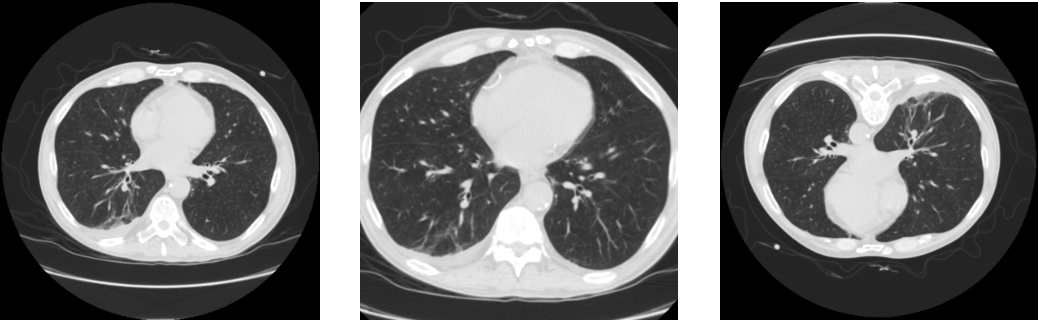

M-15: Image augmentation

Refer to caption

Figure 1: Example of image augmentations. The original image (left) has been augmented by zooming (middle) and rotation (right).

Data augmentation should only be applied after splitting the dataset into training, validation, and test sets. Although when applying image augmentation, some of the characteristics of the augmented image change, the resulting image still retains a substantial amount of information with the original image (see Figure 1). Consequently, a model could achieve high-performance measures by memorizing segmentation maps, leading to an overestimation of performance measures and models that lack generalizability. By performing augmentation only on the training set, the overall performance of the model can be improved, without compromising the integrity of the evaluation process.